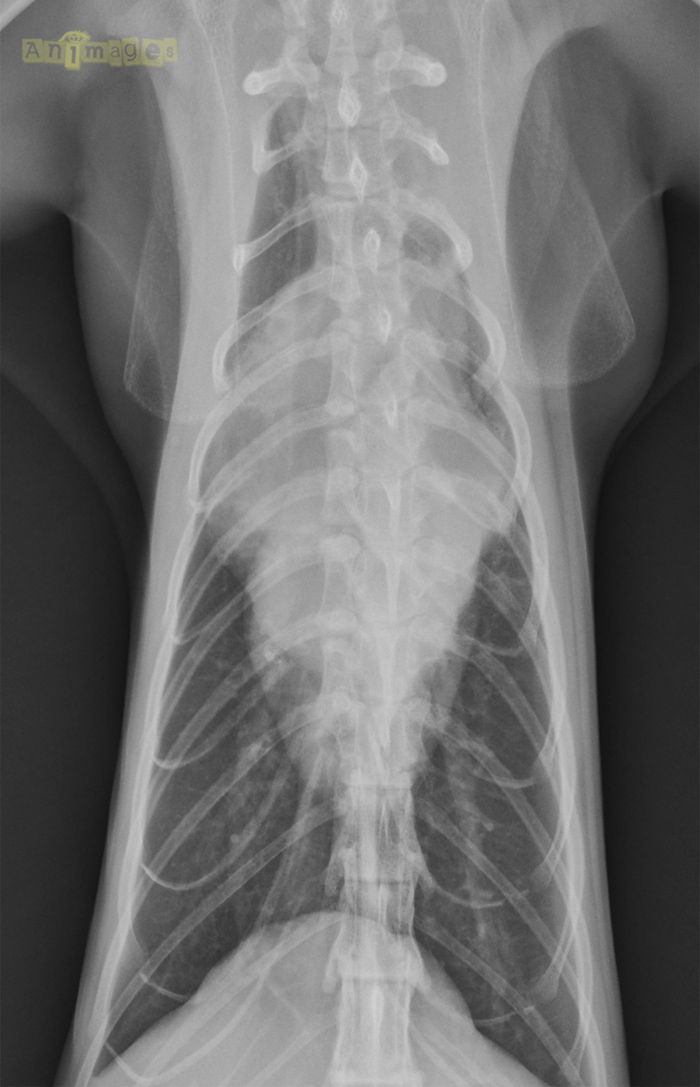

thorax VD